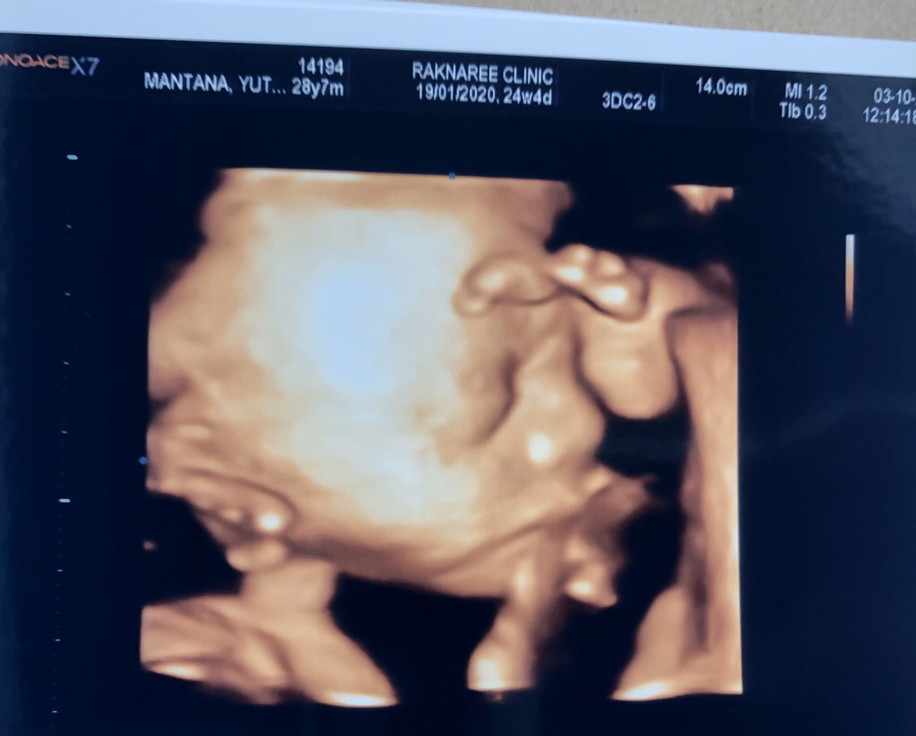

จมูกลูก

มีบ้านไหนซาวด์แล้วจมูกโด่งแบบนี้มั้ยคะ ออกมาจมูกน้องโด่งแบบนี้รึเปล่า? นี่คุณหมอบอกโด่งมาก?

โด่งเหมือนกันจ้า เห็นจมูกเป็นอันดับเเรกเลย ซาวด์ตอน5เดือยค่ะ

บ้านนี้ตอน 30 week ค่ะ ลุ้นตอนออกมาเหมือนกันค่ะ ดั้งจะหายมั้ย 😄

ลูกชายบ้านนี้ 26w ครับผม รอลุ้นว่า ออกมาจมูกจะโด่งมั้ยครับ